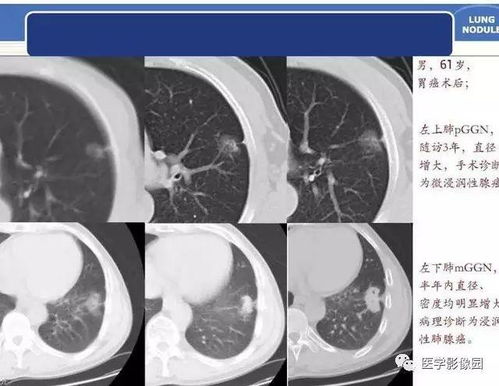

5. 肺部疾病诊断

CT医学影像系统可以检测肺部病变,如肺炎、肺结核等,对于肺部疾病的诊断和评估具有重要作用。